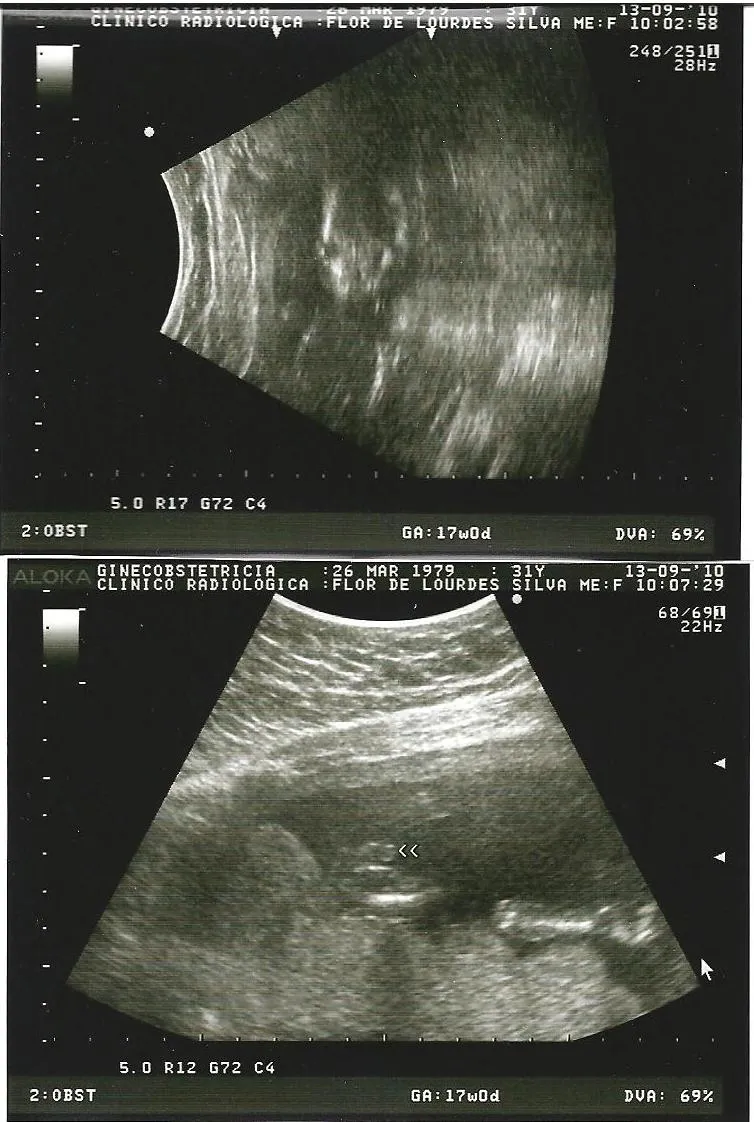

All comments on ultrasonido 19 semanas de embarazo - YouTube

El Ultrasonido es generalmente utilizado para: